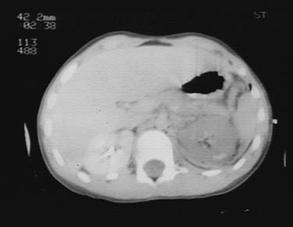

Traumatism abdominal inchis

Leziune de pancreas ( ambele foto)